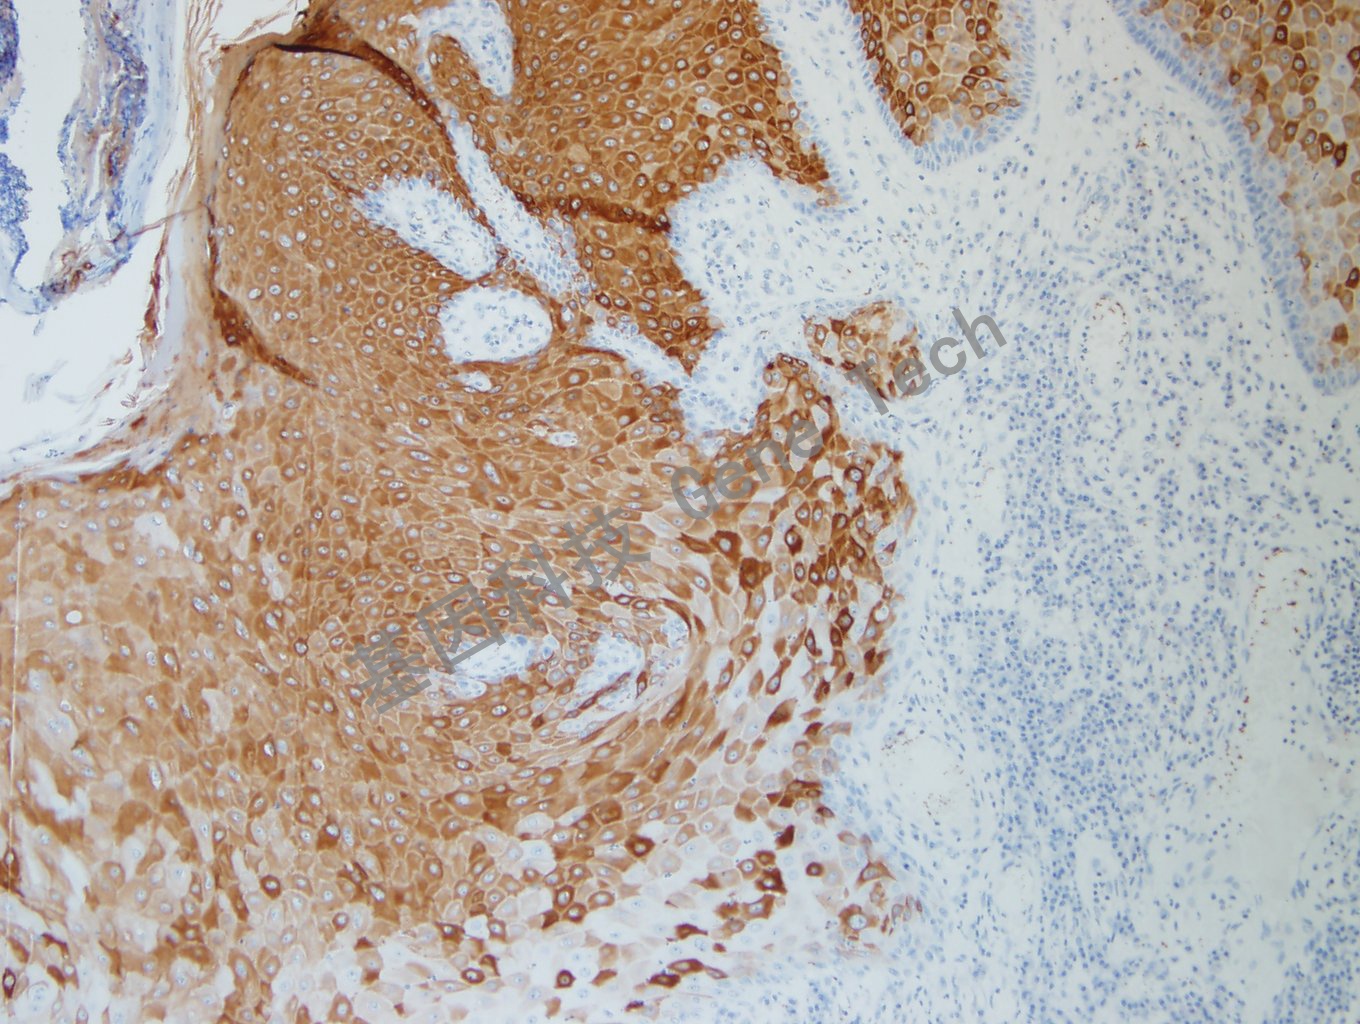

CK10( 细胞角蛋白10) 在表皮的上基层细胞中表达。在上皮细胞中,CK10 的表达与细胞的分化程度相平行;在基底层细胞中无表达,在初层细胞中开始出现,随着向粒细胞层表达逐渐增多。CK10 的表达与恶性角质细胞的成熟相关联,优先出现在分化程度更高的部位。

皮肤石蜡切片,用 CK10(GT2147)染色,细胞浆阳性,DAB 显色。